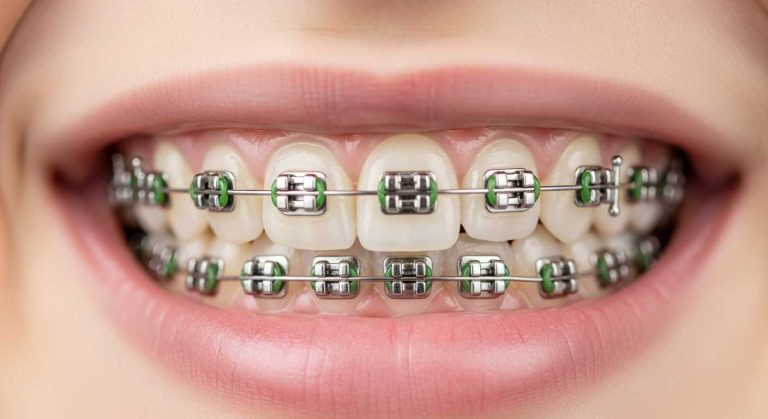

ارتودنسی:

در بسیاری از موارد خفیف تا متوسط، استفاده از بریس ها می تواند با اصلاح موقعیت دندان ها و فک به بهبود تقارن کمک کند.